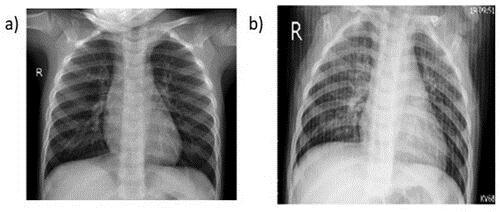

The initial dataset from the Guangzhou Women and Children'sMedicalCenterhad5836imagesaltogether.Both healthyindividualsandpneumoniapatientsweredepicted in the pictures. There were 1583 photographs of healthy chest X-rays and 4273 images of chest X-rays with pneumonia.Atrainingsetwith5136imagesandatestset with700imageswerecreatedfromtheentiredataset.The figureshowsthefirsttwoexampleimagesfromthedataset.

Figure1:ChestX-rayofahealthyperson(a)andaperson sufferingfrompneumonia(b). Figure2:Resultantimagesafterusingaugmentation techniques.